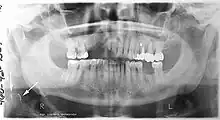

Epidemiology: general public and high risk groups

Additional research projects have further determined the prevalence rate of these atheromas in the general population (3–5%)[8][9] and among high-risk groups (over 25% in: recent stroke victims,[10] individuals with obstructive sleep apnea syndrome,[11][12][13] postmenopausal women,[14] type 2 diabetics,[15][13][16] individuals with dilated cardiomyopathy,[17][13] and among individuals who have received radiotherapy directed at the neck,[18][19]). These findings have been corroborated by other several other researchers.[20][21][22][23][13]